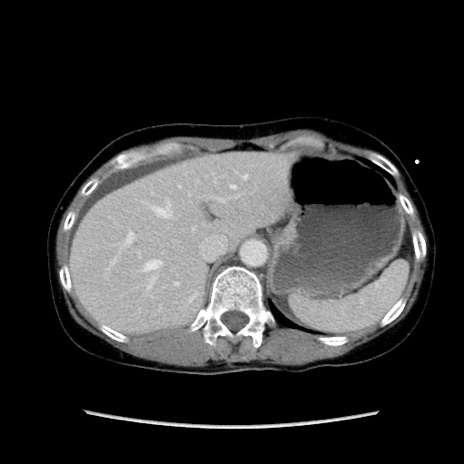

冠状断像

【症例】40歳代 女性

【主訴】上腹部痛、嘔気・嘔吐

【現病歴】約9時間前頃から急に上腹部痛、嘔気、嘔吐が出現。改善しないため救急要請。

【既往歴】子宮頚癌(広汎子宮全摘術、放射線療法)、腸閉塞

【身体所見】腹部:平坦、軟、腸雑音亢進、上腹部を中心に腹部全体に圧痛あり。

【データ】WBC 8400、CRP 0.03